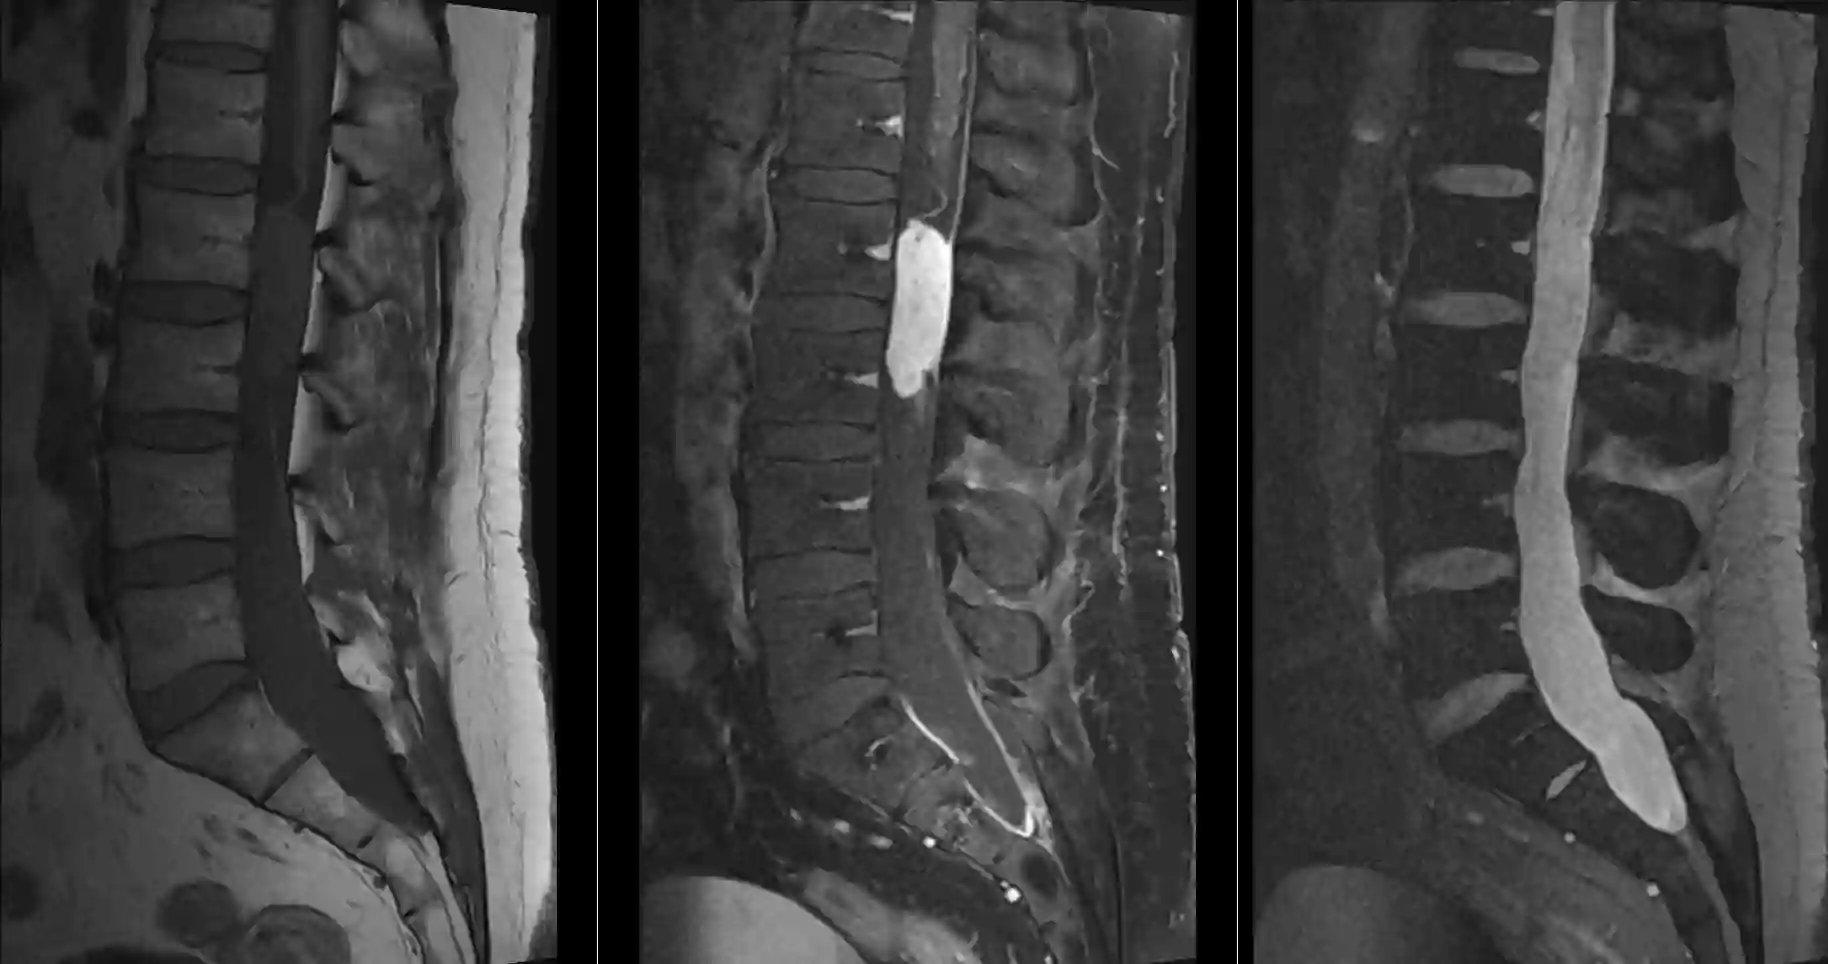

Myxopapilläres Ependymom im MRI

Sagittale MRI Bilder eines Myxopapillären Ependymoms. Links: T1 ohne Kontrastmittel, Mitte: T1 mit Kontrastmittel, Rechts: T2.